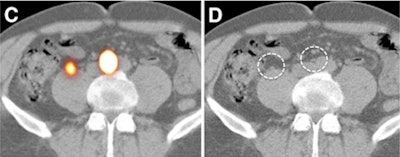

| (C) The laparoscopic sentinel node procedure uses a portable gamma camera and laparoscopic gamma ray detection probe. (D) The pre-excision image (left screen) acquired with the portable gamma camera shows both sentinel nodes. After excision (right screen), no significant remaining activity is seen. All images courtesy of the Journal of Nuclear Medicine. |

Localization of the sentinel node by the portable gamma camera was aided through the use of an iodine-125 brachytherapy seed placed on the tip of the laparoscopic probe, which aided physicians in seeing the location of the probe relative to the sentinel node.